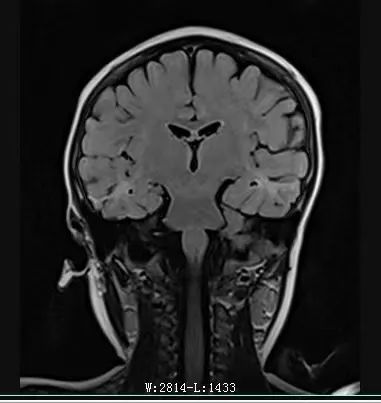

MRI:雙側(cè)額葉,雙側(cè)顳葉異常信號伴萎縮